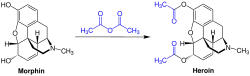

Diamorphine is produced from acetylation of morphine derived from natural opium sources, generally using acetic anhydride.[88]

Diamorphine was first synthesized in 1874 by C. R. Alder Wright, an English chemist working at St. Mary's Hospital Medical School in London who had been experimenting combining morphine with various acids. He boiled anhydrous morphine alkaloid with acetic anhydride for several hours and produced a more potent, acetylated form of morphine which is now called diacetylmorphine or morphine diacetate. He sent the compound to F. M. Pierce of Owens College in Manchester for analysis. Pierce told Wright:

Wright's invention did not lead to any further developments, and diamorphine became popular only after it was independently re-synthesized 23 years later by chemist Felix Hoffmann.[93] Hoffmann was working at Bayer pharmaceutical company in Elberfeld, Germany, and his supervisor Heinrich Dreser instructed him to acetylate morphine with the objective of producing codeine, a constituent of the opium poppy that is pharmacologically similar to morphine but less potent and less addictive. Instead, the experiment produced an acetylated form of morphine one and a half to two times more potent than morphine itself. Hoffmann synthesized heroin on 21 August 1897, just eleven days after he had synthesized aspirin.[94]